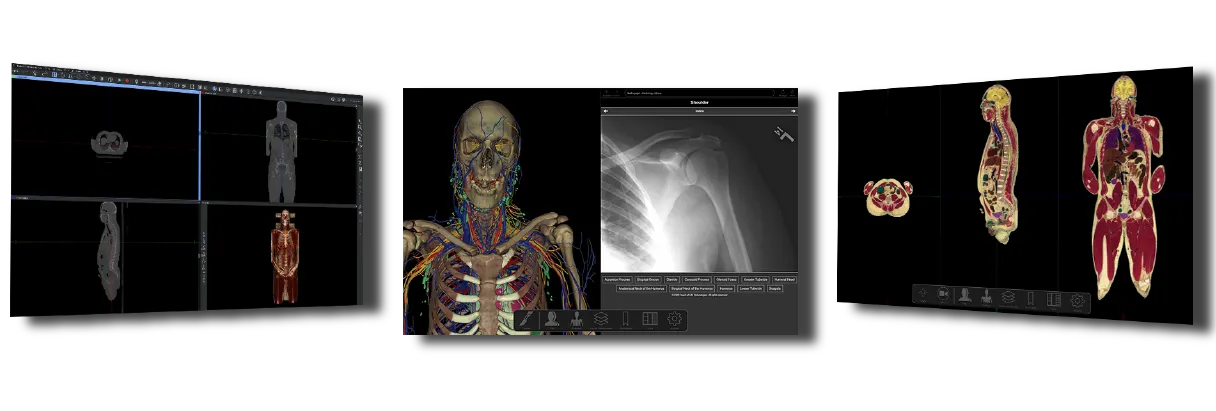

SIT Anatomy

La mesa SIT Anatomy es una solución versátil de alta tecnología con modelos 3D basados en cadáveres reales y renderizados foto realísticamente. Ofrece:

Visualización de imágenes DICOM y PACS